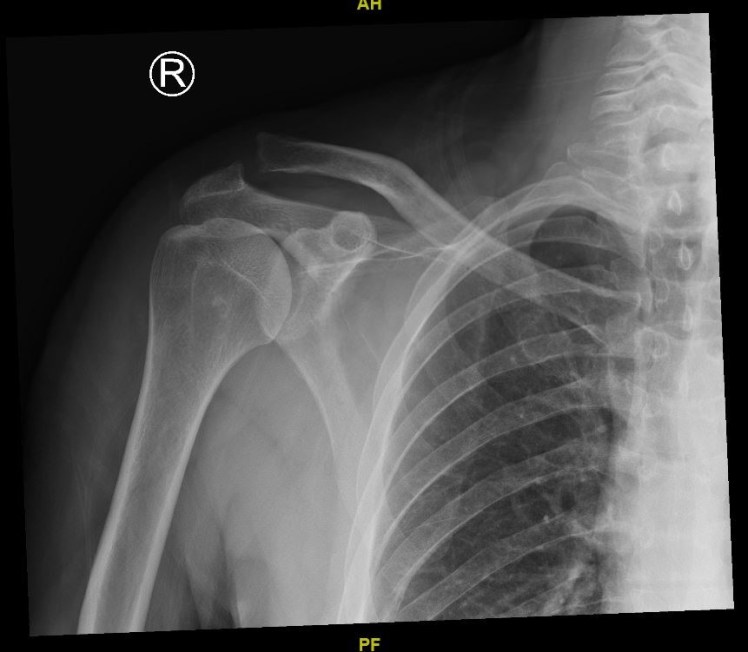

What’s the Diagnosis? Gepost op 24 februari 2019 door netwerkvsseh What’s the Diagnosis? @emdaily.cooperhealth.org Dit delen: Delen op X (Opent in een nieuw venster) X Share op Facebook (Opent in een nieuw venster) Facebook Delen op LinkedIn (Opent in een nieuw venster) LinkedIn E-mail een link naar een vriend (Opent in een nieuw venster) E-mail Afdrukken (Opent in een nieuw venster) Print Vind-ik-leuk Aan het laden... Gerelateerd